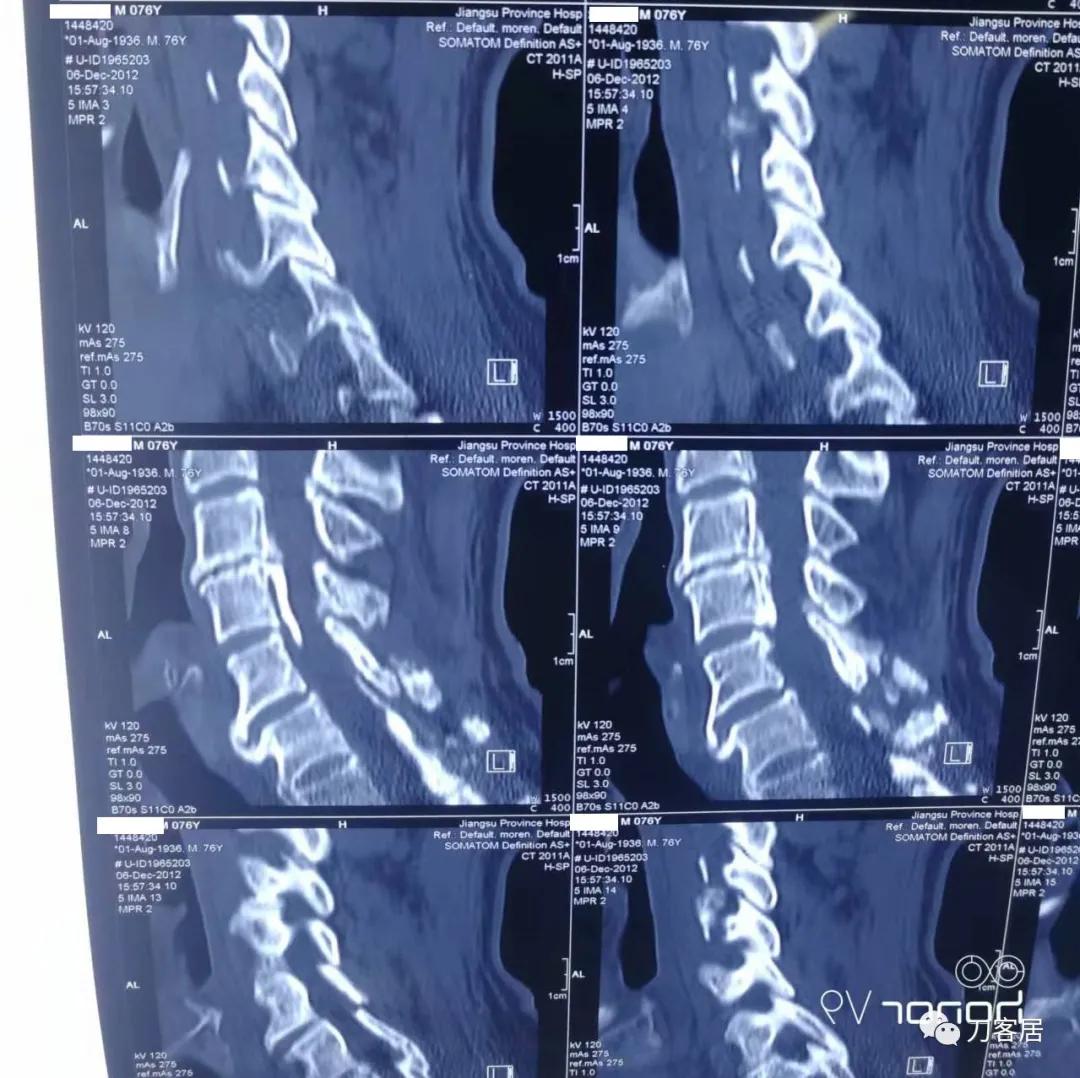

图19. 2012年12月6日颈椎椎管成形术前三维CT重建